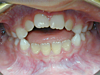

Cas 1

Enfant de 8 ans, béance incisive importante due au pouce et à la langue. Correction progressive après arrêt du pouce et travail sur la position de la langue.